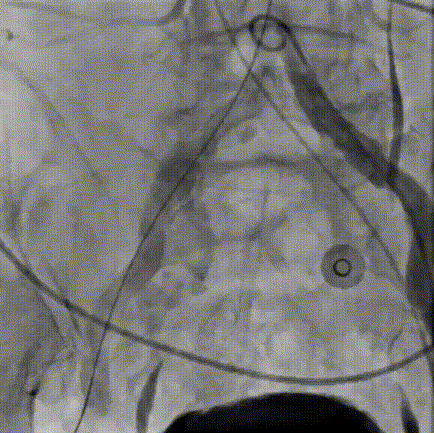

9. 交换超硬导丝入左心室,选用23mm TaurusAtlas球囊进行预扩;

10. TaurusElite输送器顺畅过弓;

11. 造影辅助零位定位释放;

12. 第一次释放至工作位,造影、超声评估瓣膜同轴性较差;

13. 遂予以回收;

14. 第二次释放至工作位,评估瓣膜形态良好,遂予以释放;

15. 造影示中度瓣周漏,决定予以后扩;

16.选用25mm TaurusAtlas球囊进行后扩;

17. 后扩后见瓣周漏改善明显,导管测压得压差为0mmHg,超声测量血流动力学指标良好。

18.外周造影未见造影剂渗漏或潴留,手术成功!